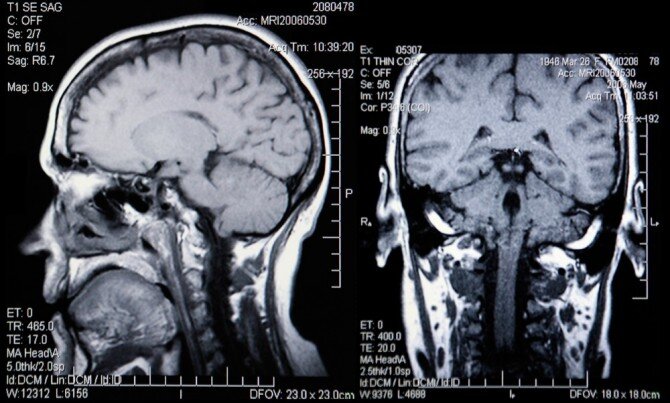

В головном мозге

В кистозном образовании находится жидкость, поэтому киста выглядит как опухоль, которая по истечению некоторого времени может увеличиваться. В головном мозге данный вид опухоли может развиться в любом отделе, но чаще всего она находится в путинной сетке коры полушарий, так как это вещество очень уязвимо. Киста головного мозга подразделяется на церебральную и арханоидальную.

В случае если киста арханридальная, тогда кистозная жидкость собирается внутри слоя из клеток мозга. Причинами её возникновения могут быть болезни или травма. Если же киста церебральная, она будет заполнять некротические образования. Чаще всего появляется после инсульта. Когда заболевание имеет начальную стадию, проходит бессимптомно. В процессе развития болезни, кистозная жидкость начинает мешать нормальному протеканию крови, может появиться ощущение давления внутри черепа, мигрень, шумы в ушах.

В случае если зафиксированы данные симптомы, призывник может рассчитывать на получение военного билета. Если же проявляется умеренная стадия протекания заболевания, призывник не идёт служить в армию, но при этом, в случае мобилизации он будет призван в службе. Если же заболевание протекает без симптомов, либо же с лёгкими симптомами, призывник будет годен к службе в армии. Стоит знать, что такой вид заболевания может быть обнаружен только с помощью МРТ. Поэтому, если киста была выявлена до призыва, нужно пройти все обследования и представить документы военной медицинской комиссии.